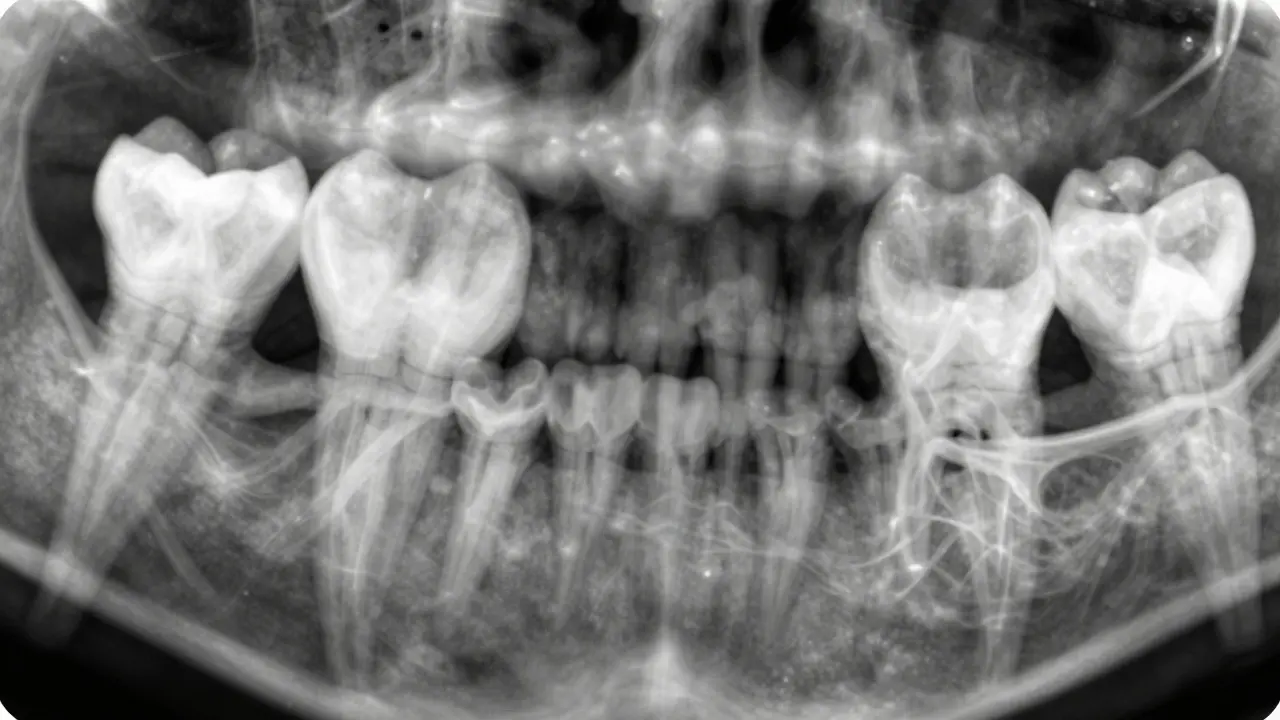

Rentgenový snímek předních zubů s tmavou oblastí kolem kořene označující zánět okostice.

Nejprve vás vyslechne - jak bolest vznikla, jak se mění, co jste dělali, když jste si to všimli. Pak provede prohlídku: zatlačí na dásně, zkontroluje citlivost, podívá se na barvu zubu. Ale klíčový krok je rentgen. Na snímku je vidět, zda se kolem kořene zubu objevila tmavá oblast - to je přesně místo, kde kost zaniká kvůli infekci. Tato tmavá oblast se nazývá „radiolucence“ a je jasným znakem zánětu okostice.